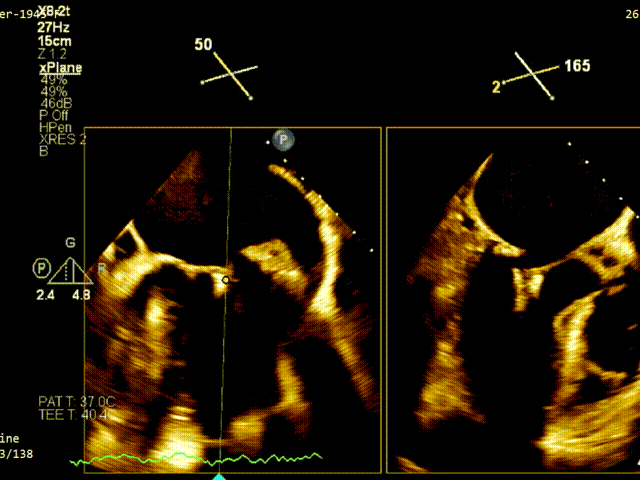

术前TEE评估

经食道超声提示,患者二尖瓣P1 commissural脱垂、腱索断裂合并重度反流(Carpentier II型/DMR4+)。

二尖瓣后瓣环明显钙化;主动脉瓣轻度钙化;三尖瓣中度功能性反流(FTR2+)。左房明显扩大;左室壁非对称性肥厚,以室间隔基底段肥厚为著(HOCM)。左室整体收缩功能正常。

二尖瓣环AP径33mm,二尖瓣后瓣环明显钙化,房间隔拟穿刺高度40mm;二尖辦脱垂宽度5.7mm,脱垂高度7.7mm,二尖瓣1区前叶长度29mm,后叶长度19mm,二尖瓣2区前叶长度23mm,后叶长度14mm,MVA=4.0cm²。

术前1区X-Plane反流情况